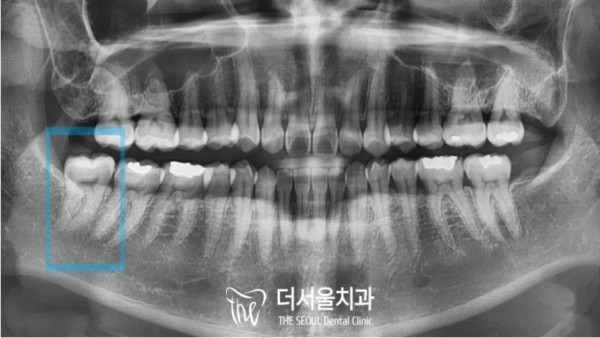

환자분의 치아 엑스레이 사진을 보아도

사랑니가 곧게 맹출되어 있는것이 보입니다.

이렇게 자란 사랑니는 빠르게 뽑을 수 있습니다만

그 전에 꼭 '하치조 신경관'과의 거리를 확인해야 합니다.

Even if you look at the x-ray of your teeth

I can see that the wisdom tooth is out straight.

You can pull out wisdom teeth that grew like this quickly

Before that, make sure to check the distance from the 'lower alveolar nerve tube'.

파노라마 엑스레이로 보았을때에는 신경관과

사랑니 뿌리가 아주 가까워 보이는것이 문제인 상황입니다.

저 신경을 잘못건드리면 안면마비, 신경손상... 아주 큰 부작용이 생길 수 있습니다.

Panorama X-ray shows that the neural tube and

The problem is that the wisdom tooth roots look very close.

If you touch those nerves incorrectly, you can have very big side effects, like facial paralysis, nerve damage.